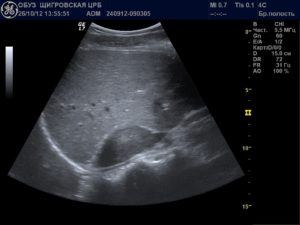

Пациент при процедуре находится в нескольких положениях: горизонтально – на спине и на боку, вертикально и сидя. На предварительно освобожденную от одежды кожу наносится специальный гель для улучшения распространения ультразвуковых волн.

Затем с помощью плавного перемещения датчика врач изучает параметры почечной паренхимы и чашечно-лоханочной системы.

Что показывает УЗИ почек и мочевого пузыря? В протоколе исследования указываются:

- количество и расположение почек;

- их подвижность;

- структура чашечно-лоханочной системы;

- описание эхогенности паренхимы;

- анатомические особенности мочеточников;

- подробная характеристика выявленных плотных и жидкостных образований при их наличии.

Описывает и выносит заключение врач ультразвуковой диагностики. Обследование покажет пороки развития, опухолевые и воспалительные патологии, мочекаменную болезнь, дистрофические процессы. Выявить нарушение почечного кровотока можно с помощью допплерографии.